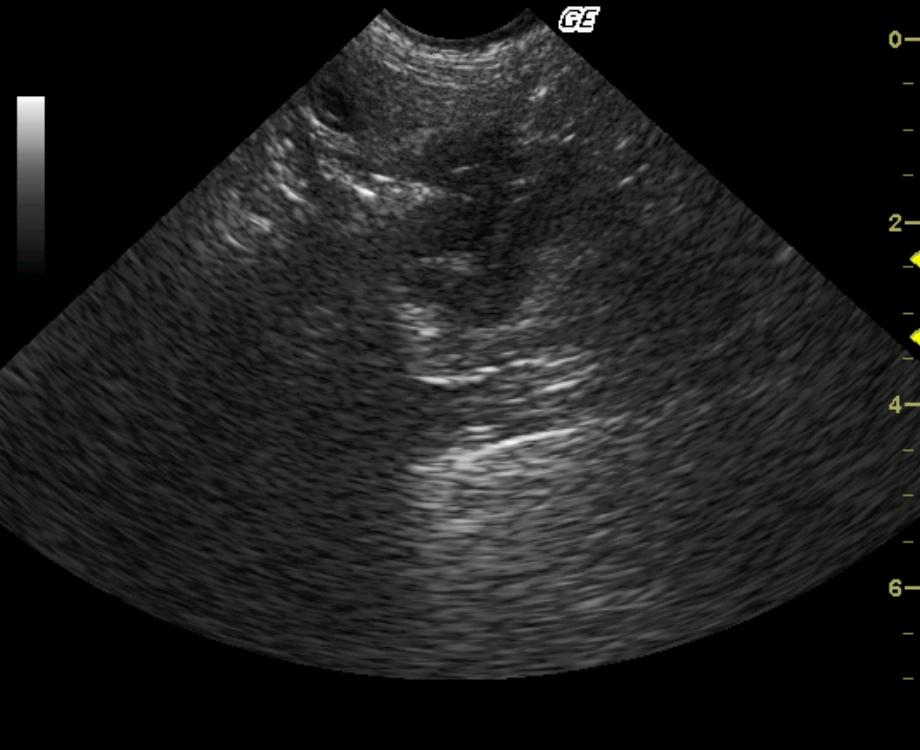

Marked, asymmetrical, focal bowel wall thickening is present. Transmural involvement is suspected; however, in certain regions the thickening appears to be involving and potentially arising from the muscularis layer. The peripheral borders of the mass are slightly lobulated; however, the serosal layer appears to be intact supporting encapsulation.

Intestinal neoplasia, complicated inflammatory lesion is less likely.